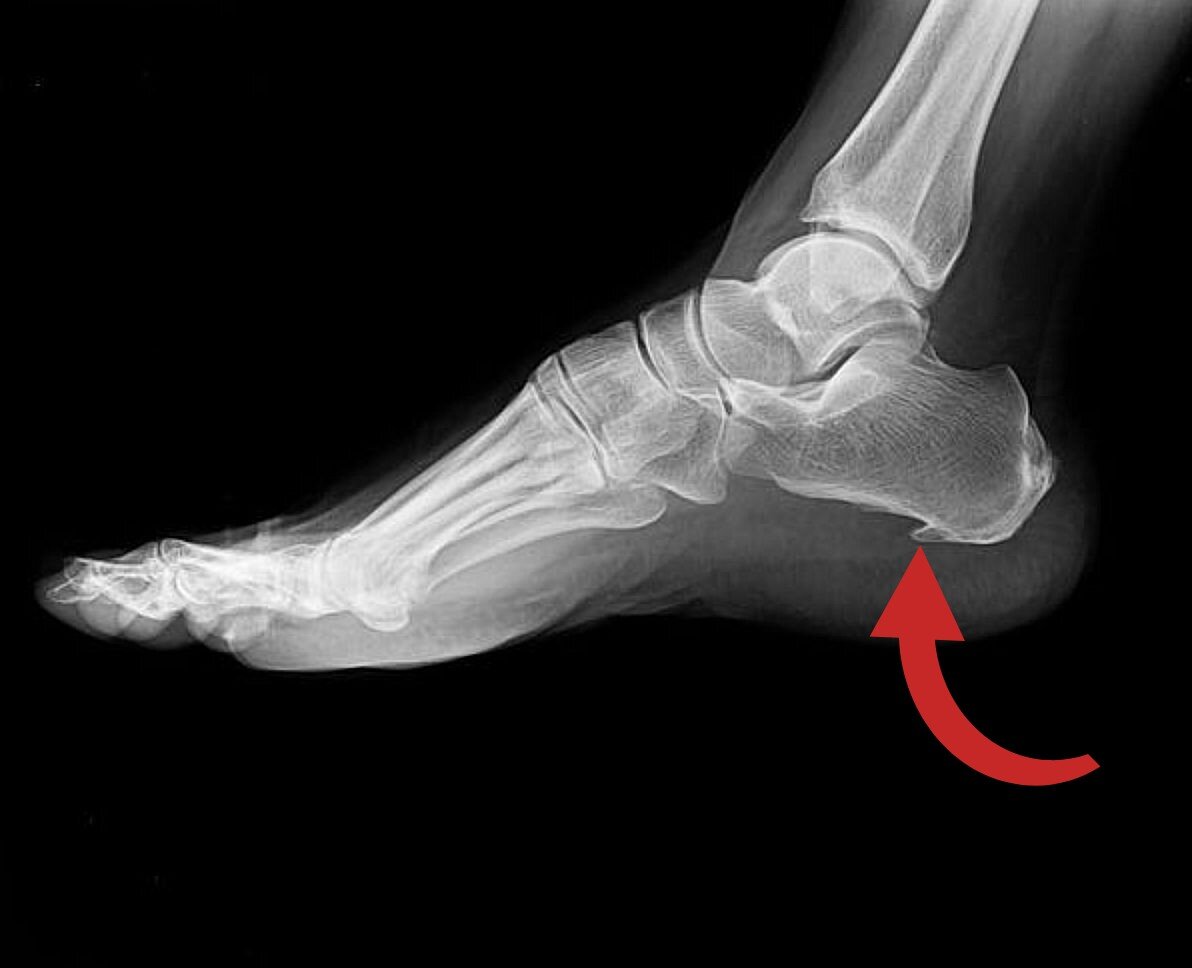

Пяточная шпора – остеофит пяточной кости

Рентгенография пяточной кости

Рентгенография пяточной кости позволяет врачу увидеть наличие остеофита (костного нароста) и его размеры. Это важный метод для подтверждения диагноза.